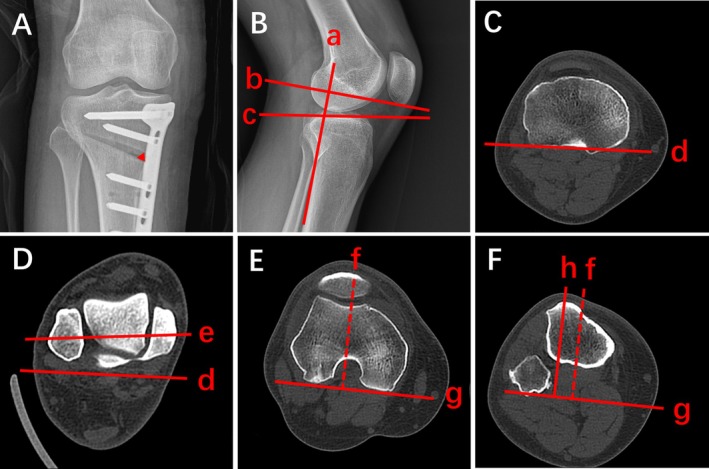

Methods: Patients who underwent STB-MOWHTO for varus knee deformity at our hospital were reviewed retrospectively from January 2020 to December 2022. Radiographic parameters, including opening width (OW), distal tibial rotation (DTR), posterior tibial slope (PTS), and TT-TG distance, were assessed before operation and directly postoperatively. Multivariate mixed linear regression analyses were employed to investigate the relationships between OW, the changes in DTR, PTS, and TT-TG distance. Restricted cubic spline curve fitting and threshold effects were used to assess potential non-linear relationships between the independent variables and changes in TT-TG distance. Stratification analysis was conducted to assess the stability of the results.

目的:在结核上双平面内侧开口楔形高位胫骨截骨术(STB-MOWHTO)中冠状、矢状和轴向排列的变化可能对胫骨结节-滑车沟(TT-TG)距离有不同的影响,但很少有文献讨论这一特定问题。我们的目的是分析STB-MOWHTO期间不同平面的排列变化对TT-TG距离的影响。方法:回顾性分析2020年1月至2022年12月在我院行STB-MOWHTO治疗膝内翻畸形的患者。术前和术后直接评估影像学参数,包括开口宽度(OW)、胫骨远端旋转(DTR)、胫骨后斜率(PTS)和TT-TG距离。采用多元混合线性回归分析,探讨OW与DTR、PTS、TT-TG距离变化的关系。使用限制三次样条曲线拟合和阈值效应来评估自变量与TT-TG距离变化之间潜在的非线性关系。分层分析评价结果的稳定性。结果:纳入66例患者的102个膝关节。TT-TG距离变化与OW呈正相关(β = 0.551, 95% CI: 0.340, 0.762, p)。结论:STB-MOWHTO期间TT-TG距离变化与OW、DTR变化呈线性正相关。OW每增加1 mm, TT-TG距离平均增加0.551 mm。DTR每增加1°,TT-TG距离平均增加0.284 mm。证据等级:三级。